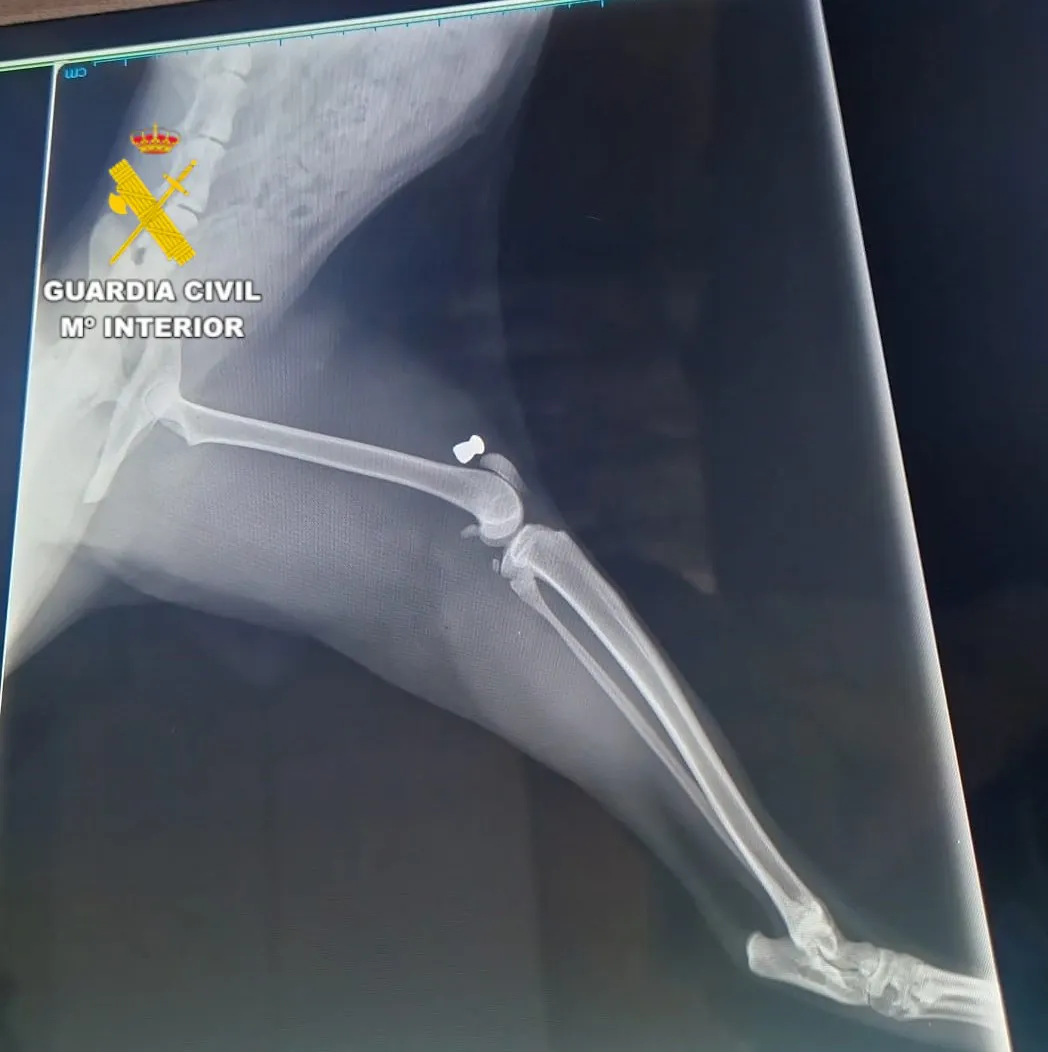

La investigació es va iniciar el mes de setembre, quan els agents del SEPRONA van tindre coneixement de la mort de tres felins i de l’existència d’altres dotze animals que presentaven ferides. Les primeres diligències van permetre comprovar que les lesions eren compatibles amb les produïdes per l’impacte de perdigons disparats amb una carabina d’aire comprimit.

Un examen veterinari posterior va confirmar aquestes sospites en detectar diversos perdigons incrustats al cos dels animals. Després de diverses tasques d’investigació i gestions de camp, els agents van poder identificar, localitzar i investigar el presumpte responsable dels fets, un veí de Geldo de 62 anys, al qual se li van intervenir dues carabines d’aire comprimit presumptament utilitzades per cometre els actes.